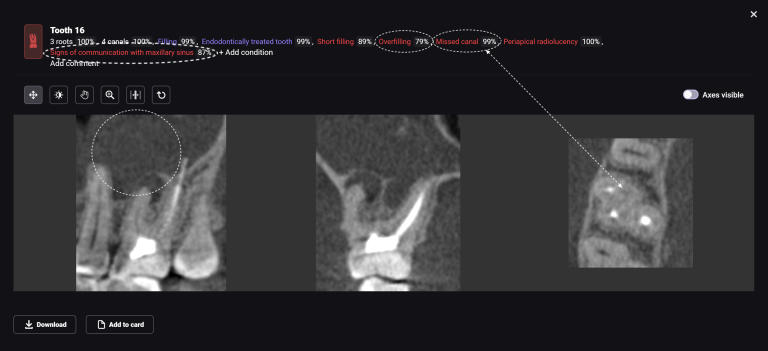

The second mesio-buccal (MB2) canal is notorious for being difficult to identify and is often left untreated, this can directly influence the outcome of the final treatment

Diagnocat AI helps us to see not only the consequences, but also the causes of the pathology. For example, in this clinical case – the missed MB2 during previous endodontic treatment of tooth 26 (Universal 14)